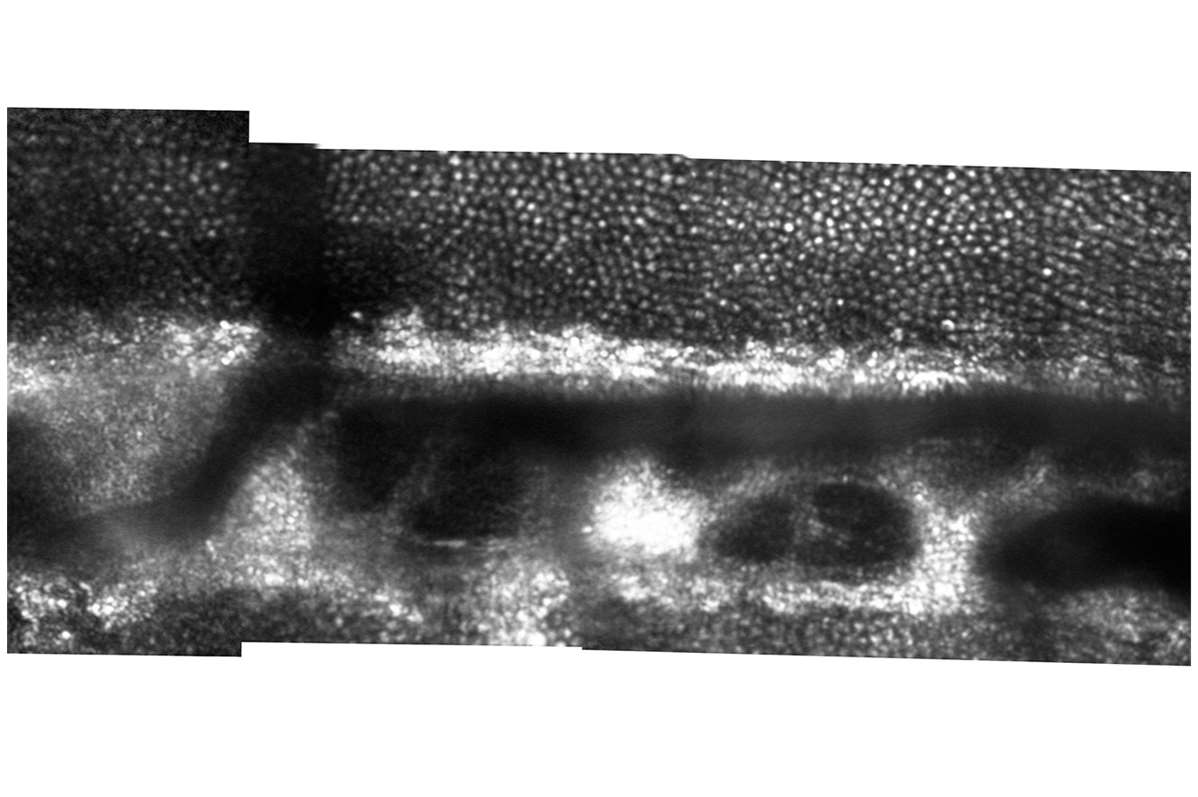

Cystoid Macular Edema in Retinitis Pigmentosa

The bubbled appearance of the top image (AOSLO montage of the photoreceptor mosaic) is caused by the presence of numerous cystic structures in the inner retina (seen in the lower OCT image).